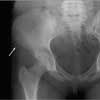

The patient was taken to the local emergency department (ED) immediately after her injury, where she was told that her pain was caused by a severe muscle sprain. She was sent home with analgesics. Her mother later received a call from the emergency department physician who told her that a radiologist had viewed the x-ray films and had diagnosed an avulsion fracture (Figures). The ED physician recommended a bone scan to rule out decreased bone mineral density "because young girls should not get hip fractures."

Fractures of the extremities occur frequently, but involvement of the trunk and pelvis--as in the case of this patient--is uncommon. An avulsion fracture of the pelvis occurs when a muscle contracts very forcefully, pulling off a piece of bone where the muscle and tendon connect. This fracture seldom occurs in children younger than 12 years but is particularly common in teenaged athletes.3 Groin injuries occur in 5% to 9% of high school athletes from a sudden acceleration-deceleration or directional change during sporting events.3

The treatment of trampoline mishaps is injury-specific. In our patient's case, an orthopedic consultation was obtained. The orthopedist agreed with the diagnosis of avulsion fracture based on the radiographic findings and did not recommend a bone scan. Rest and symptomatic relief were prescribed, and the fracture was allowed to heal.